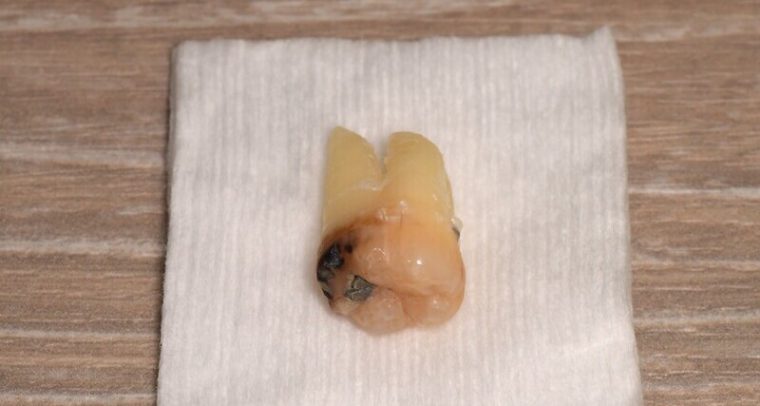

CASE 26

| 年齢・性別 | 26歳・男性 |

| 主訴 | 主訴:左下の親知らずが黒くなっている 部位:左上下親知らず |

| 親知らずのはえ方 | 真っ直ぐ生えている |

| 抜歯期間 | 30分 |

| 抜歯費用 | 約2,500円(保険診療3割負担) (2023年4月現在) |

| 抜歯内容 | 左上下親知らず抜歯 |

| 治療方針 | 左下親知らずが黒くなっているとのことでご来院されました。 左上下の親知らずが虫歯になっていたため、抜歯を行いました。 |

| 特記事項 | 抜いた所を舌や指でさわると出血や細菌感染する恐れがありますので、刺激しないようご注意ください。 出血が続く場合は、清潔なティッシュを30分間しっかり噛んで様子をみてください。 |

| 担当者所見 | 垂直に生えていたため、時間を要することなく抜けました。 |